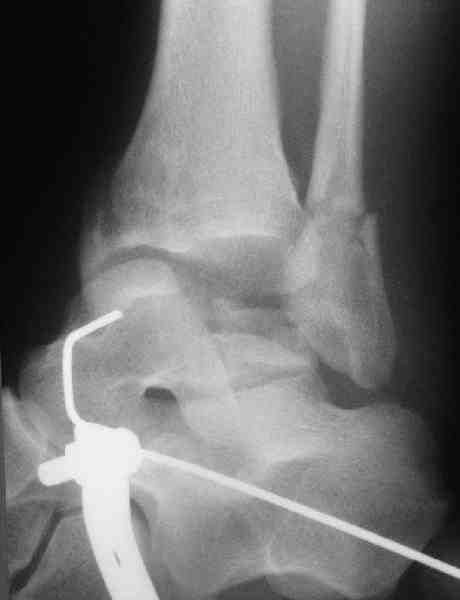

Два фрагмента суставной поверхности тарана можно восстановить боковой компрессией шурупами и дополнительно костная пластика.

(кстати, на нашем случае была применена костная пластика-allograft crouton для заполнения дефектов)

Наружный фиксатор "голень-пятка", "лигаментотаксис" при поступлении, домой через 48 часов после обучения ходьбы на костылях, в течение ближайшего времени осмотр в поликлинике для определения кондиции мягких ткани (тест на образование морщин в зоне разреза), при отсутствии отека примерно на 6-7 день с момента травмы операция.